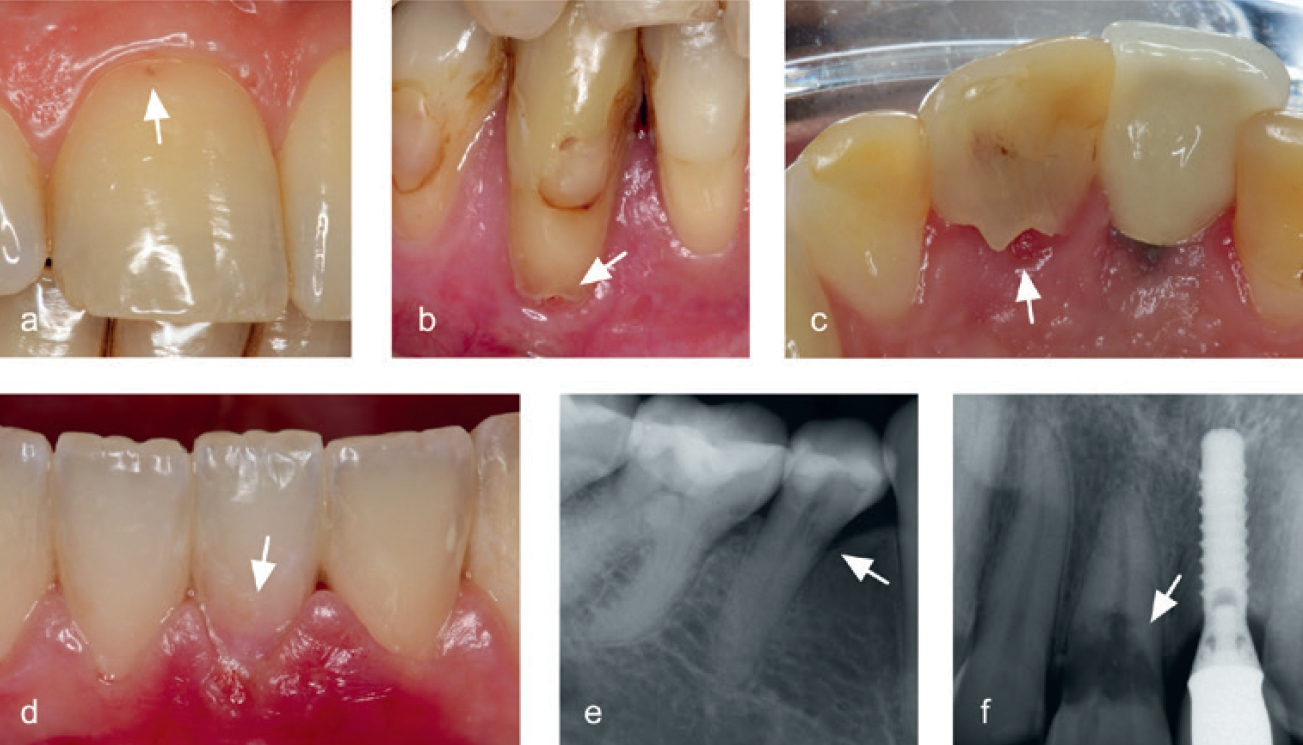

Sie verläuft häufig symptomfrei und wird oft im Rahmen von Routineuntersuchungen entdeckt. Es sind in der Regel tastbare zervikale Defekte vorzufinden, die mit Granulationsgewebe gefüllt sind, welches bei Berührung stark blutet (Abb. 7a bis c). Eine zunehmende Ausbreitung des hyperplastischen Resorptionsgewebes verursacht großräumige Defekte, die sich als rötliche Verfärbungen der Zahnkrone, sogenannte Pink-Spot-Läsionen, zeigen können (Abb. 7d). Radiologisch stellt sich die invasive zervikale Resorption meist als wolkige Aufhellung im Bereich des Zahnhalses dar (Abb. 7e und f). Ein typisches Merkmal ist auch das unversehrte perikanaläre Dentin, was als „Pericanalar Resorption Resistant Sheet“ (PRRS) bezeichnet wird [25,26]. Wie bereits erwähnt, ist Prädentin äußerst widerstandsfähig gegen resorptive Prozesse und stellt sich bis zuletzt als intakte Dentinbarriere dar (Abb. 8). Die invasive zervikale Resorption verläuft in mehreren Stadien [27]. Über einen Zementdefekt (Abb. 8) dringt das entzündliche Gewebe zunächst in die Zahnwurzel ein (Initiation). Bei weiteren bakteriellen Reizen, persistierenden Krafteinwirkungen oder Gewebehypoxie breitet sich die Resorption im Zahn in alle Richtungen aus (Progression). Im Laufe der invasiven Auflösung durch das entzündliche Gewebe kommt es zu einem knochenähnlichen Remodeling von Zahnhartgewebe (Reparatur).

Während invasive zervikale Resorptionen in der Progressionsphase radioluzente Läsionen zeigen, stellen sich die Defekte in der anschließenden reparativen Phase radioopak dar.